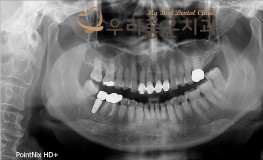

우리좋은치과 치아 상실 및 골소실 → 뼈이식 및 임플란트 보철 치료(임**2016...

No.296

임플란트

2019-05-31

1544